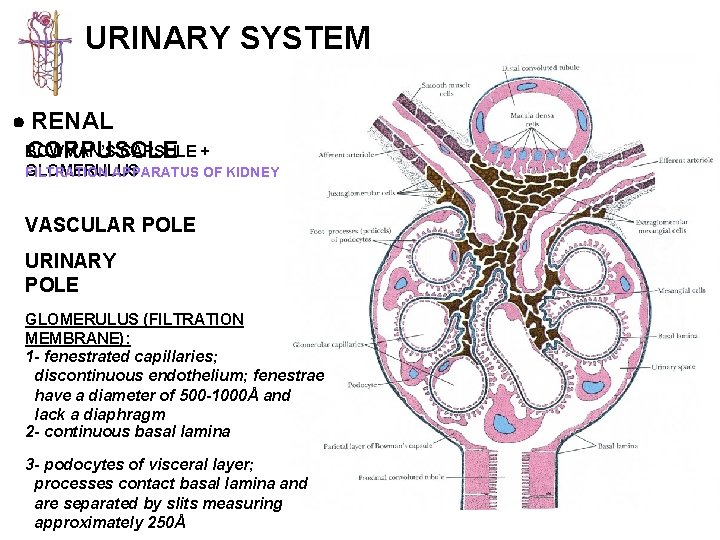

URINARY SYSTEM RENAL CORPUSCLE BOWMAN’S CAPSULE + GLOMERULUS FILTRATION APPARATUS OF KIDNEY 1. BOWMAN’S CAPSULE: - the beginning of the nephron that consists of a blind sac lined with simple squamous epithelium that is continuous with the PCT - parietal layer & visceral layer (specialized) 2. GLOMERULUS: - specialized tuft of capillaries which housed in the capsular space (10 -20 capillary loops) - blood flowing through glomerulus capillaries undergoes a filtration process to produce the initial urine filtrate

URINARY SYSTEM RENAL BOWMAN’S CAPSULE + CORPUSCLE GLOMERULUS FILTRATION APPARATUS OF KIDNEY VASCULAR POLE URINARY POLE GLOMERULUS (FILTRATION MEMBRANE): 1 - fenestrated capillaries; discontinuous endothelium; fenestrae have a diameter of 500 -1000Å and lack a diaphragm 2 - continuous basal lamina 3 - podocytes of visceral layer; processes contact basal lamina and are separated by slits measuring approximately 250Å